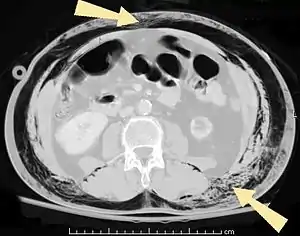

CT scan of bullous emphysema.

When the subpleural bullae are significant the emphysema is called bullous emphysema. Bullae can become extensive and combine to form giant bullae. These can be large enough to take up a third of a hemithorax, compress the lung parenchyma, and cause displacement. The emphysema is now termed giant bullous emphysema, more commonly called vanishing lung syndrome due to the compressed parenchyma.[16] A bleb or bulla may sometimes rupture and cause a pneumothorax.[11]